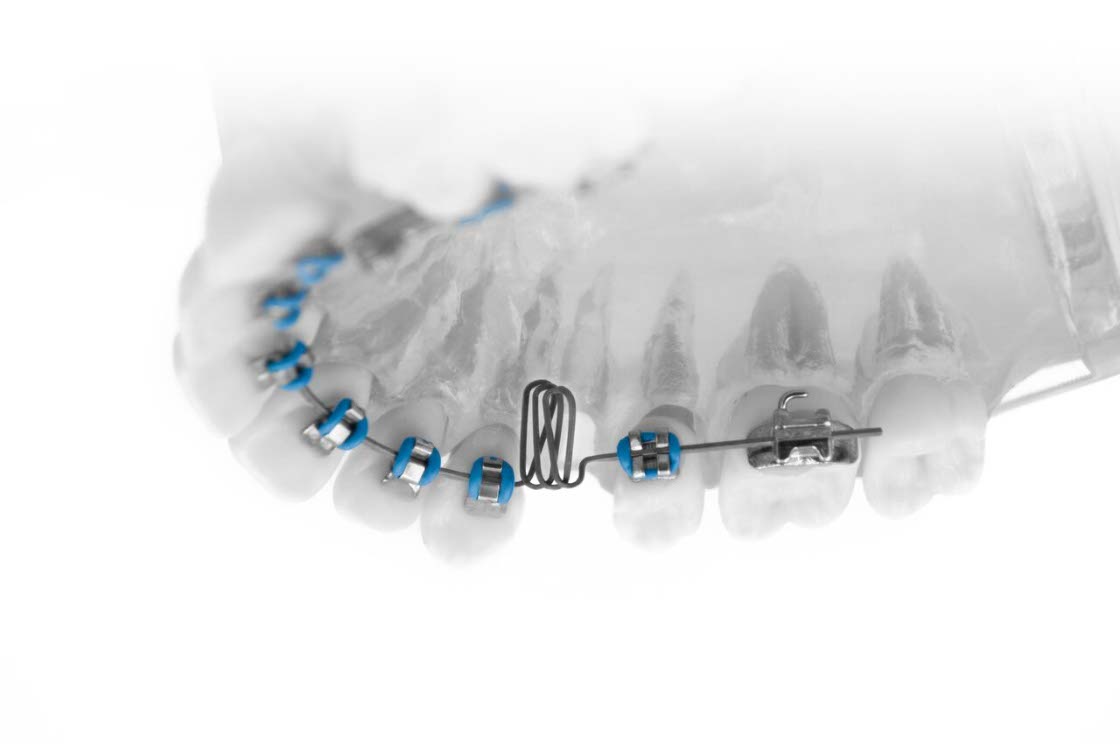

現在主流となっている「ストレートワイヤー法」は、既製のアーチワイヤーを装着する方法ですが、当クリニックでは「スタンダードエッジワイズ法」を駆使した歯科矯正治療を行っています。

スタンダードエッジワイズ法は、患者様一人ひとりの歯列に合わせて、歯科医師が手作業でワイヤーを丁寧にベンディング(曲げる)し、歯の凹凸にぴったりとフィットするようにアーチワイヤーをオーダーメイドします。複雑なループなどを設けることで、効率的かつ効果的な歯牙移動が実現できる治療法です。

しかし、この方法はベンディングに時間がかかり、患者様一人ひとりの治療時間が長くなることがあります。また、治療結果は歯科医師の技術力に大きく依存するため、難易度の高い治療法でもあります。

KR Spring

特許取得済・

弾性高分子ワイヤーの加工技術

本製品は、特に裏側矯正時に使用する「マッシュルームアーチ」を再現したもので、口腔内の形状にフィットする作りとなっています。柔軟性の高いフレキシブルワイヤーを使用し、多重ループスプリング部を設けることにより、アーチワイヤー全体を既存の物よりも長く使用することが可能となりました。

また、多重ループスプリングによるバネ効果が発生し、適度な矯正力(弱い持続的な力)を加えることができます。これらにより、以下のメリットを生み出しました。